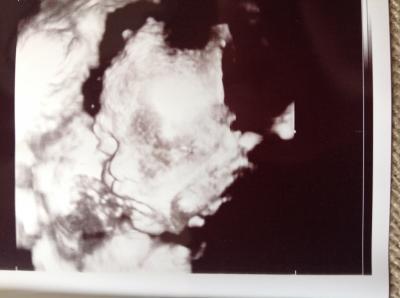

Hallo liebe Mitkuglerinnen, Wir hatten heute ein tolles 3. Screening bei 28+1. Der kleine hat sich schon in die richtige Richtung gedreht, was ich nicht gedacht hätte, weil er in den letzten Tagen so auf meiner Blase Trampolin gespielt hat. Aber man unterschätzt die vorgeburtliche Beweglichkeit. Die Füße waren auch beim Ultraschall neben dem Köpfchen zu sehen. Nunja, der kleine ist von seiner Größe schon eine Woche weiter, 41 cm! Wow. Alles sieht super aus, genug Fruchtwasser und und und. Hach ich bin verliebt und happy. Und zu alldem hat eine liebe Freundin mir heute ihre Schwangerschaft in der 13. Woche verkündet. Das freut mich auch sehr. Hoffe euch gehts auch allen prima.

Bild zu Foto und Bericht 3. Screening - Forum für Januar - Mamis

Huhu. Süsses Bild und echt schon gross...super , dass alles ok ist Lg Silke

Was für ein schönes Ultraschallbild!!! Sehr schön, dass alles glatt verläuft! ;-)

Hallo, fand das Foto gestern schon atemberaubend als du es mir via Whatsapp geschickt hast! :) Super schönes Bild und dass der Große schon so Groß ist, ist ja eigentlich nicht schlimm oder? Wir sind angeblich auch schon immer eine Woche weiter, da mache ich mir gar keinen Kopf! :)

Oh was für ein schönes Bild!!!!! Und so ein süßes Gesicht!!!!!!